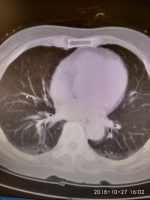

支氣管擴張伴肺部感染患者喘息、氣短3天 關鍵疾病:支氣管擴張繼發(fā)感染 慢性肺源性心臟 病心力衰竭 心功能Ⅲ級高血壓病 現(xiàn)病史【一般資料】 男性,68歲,農民 【主訴】男性,68歲,農民喘息、氣短3天入院 【現(xiàn)病史】患者入院前3天,上呼吸道感染后出現(xiàn)喘息、氣短,活動后加重,休息后可緩解呈進行性加重,伴有夜間陣發(fā)性呼吸困難及端坐呼吸;有納差及腹脹;偶有咳嗽有咳痰,為黃色粘痰,不易咳出,量不多。無頭暈,偶有頭痛,無惡心、嘔吐,無意識障礙及大小便失禁,無腹痛、腹瀉。為求診治,來我院就診,心電圖:竇性心律心律101次/分,肺型P波。肺部CT:雙側慢性支氣管炎,左下肺支氣管擴張,右下肺氣腫、肺大泡,右上肺炎性改變。以“支氣管...